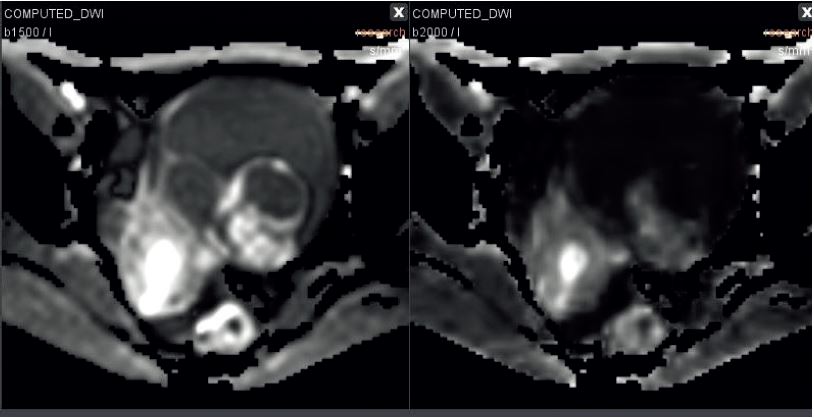

Переглядач на платформі Еnterprise завдяки комбінованій візуалізації трьох площин Т2, Т1 із насиченням жиру та без нього, дозволяє підтвердити, що ураження пов’язано з яєчником та що не знайдено наявності жиру (тип ураження дермоїд) або крові (рис. 2). Опція Olea IVIM дає змогу обчислювати дифузійно-зважені синтетичні зображення (в т.ч. з високими значеннями b), щоб полегшити діагностику більшої частини уражених тканин (рис. 3).

Рисунок 3